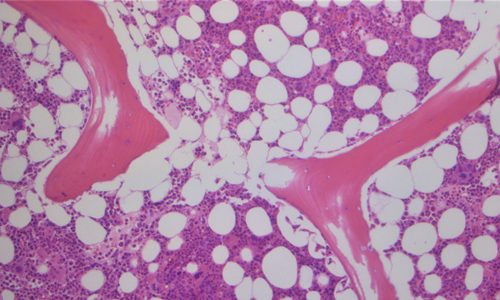

Bone Marrow Pathology

All hematologic malignancies blood cancers specific storage diseases, metastatic tumors involving bones all can be diagnosed by 1: Bone marrow Aspiration 2 – Bone marrow Trephine biopsy.

Bone marrow aspiration and bone marrow biopsy are procedures to collect and examine bone marrow — the spongy tissue inside some of your larger bones. Bone marrow aspiration and bone marrow biopsy can show whether your bone marrow is healthy and making normal amounts of blood cells. Doctors use these procedures to diagnose and monitor blood and marrow diseases, including some cancers, as well as fevers of unknown origin.